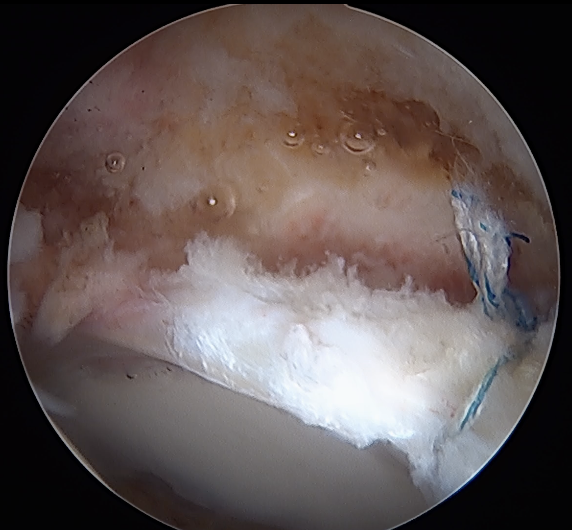

Labral Repair

Assess for Labral Tears

Expose acetabulum

- place proximal capsule suspension sutures

- elevate and protect proximal capsule for later repair

- use cautery to expose acetabulum while not injuring labrum